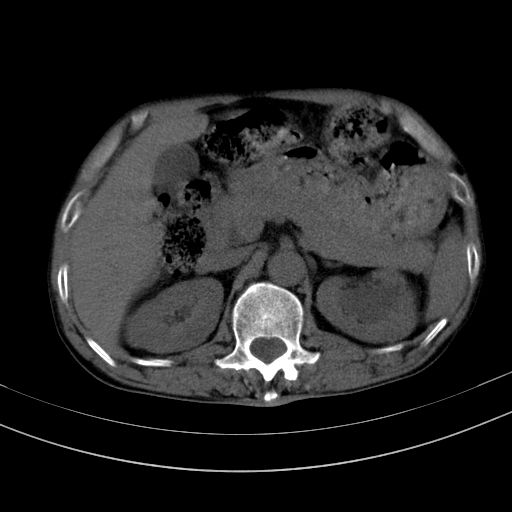

以下是引用dyqct在2010-1-9 17:56:00的发言:[br]考虑:1.双肾囊肿,左肾积水结石、旋转不良。[br] 2.右侧腹直肌血肿或纤维瘤。[br]肠道准备不好。做个增强。